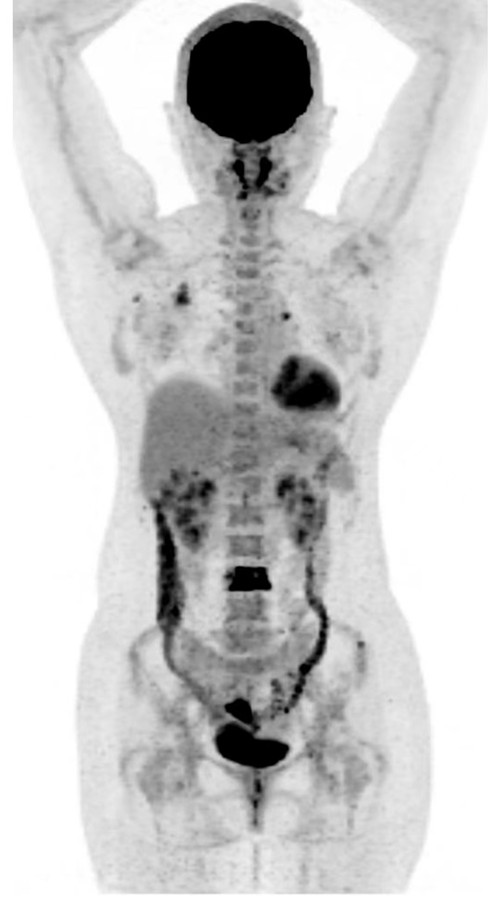

PETCT显示右侧乳腺内糖代谢明显增高的结节和腰椎的转移癌

问题来了,彭女士腰椎转移癌原发灶在哪里?是甲状腺癌吗?因关系后续治疗方案,在医生的建议下,彭女士到湖南省人民医院PET影像中心进行PET/CT扫描。检查结果让人大吃一惊,彭女士的右侧乳腺有一个糖代谢明显增高的结节,大小为10mm,高度提示右侧乳腺癌。这下解开了腰椎转移癌的谜底,乳腺癌除腰椎骨转移外,同时发现右侧腋窝淋巴结和骨盆多骨的转移。目前,彭女士已经转入乳甲外科接受手术及进一步治疗。

湖南省人民医院PET影像中心主任毛志群介绍,相当一部分癌症在患者有症状时就出现了转移,全身PET/CT检查往往能快速发现原发恶性肿瘤,为临床病理的精准诊治提供极为重要作用,避免患者因做多个检查而花费更多时间和金钱,甚至延误治疗时间。对于肿瘤标志物升高的患者通过PET/CT全身检查可以尽早发现、明确诊断,从而获得更多的治愈机会,全身进行一次检查就可以发现癌变器官。PET/CT检查对于肿瘤分期具有非常重要的意义,可以直接为临床治疗手段的选择提供依据,甚至改变治疗方案。此外,PET/CT也是各种恶性肿瘤术后监测的利器,尤其是血液系统恶性肿瘤。